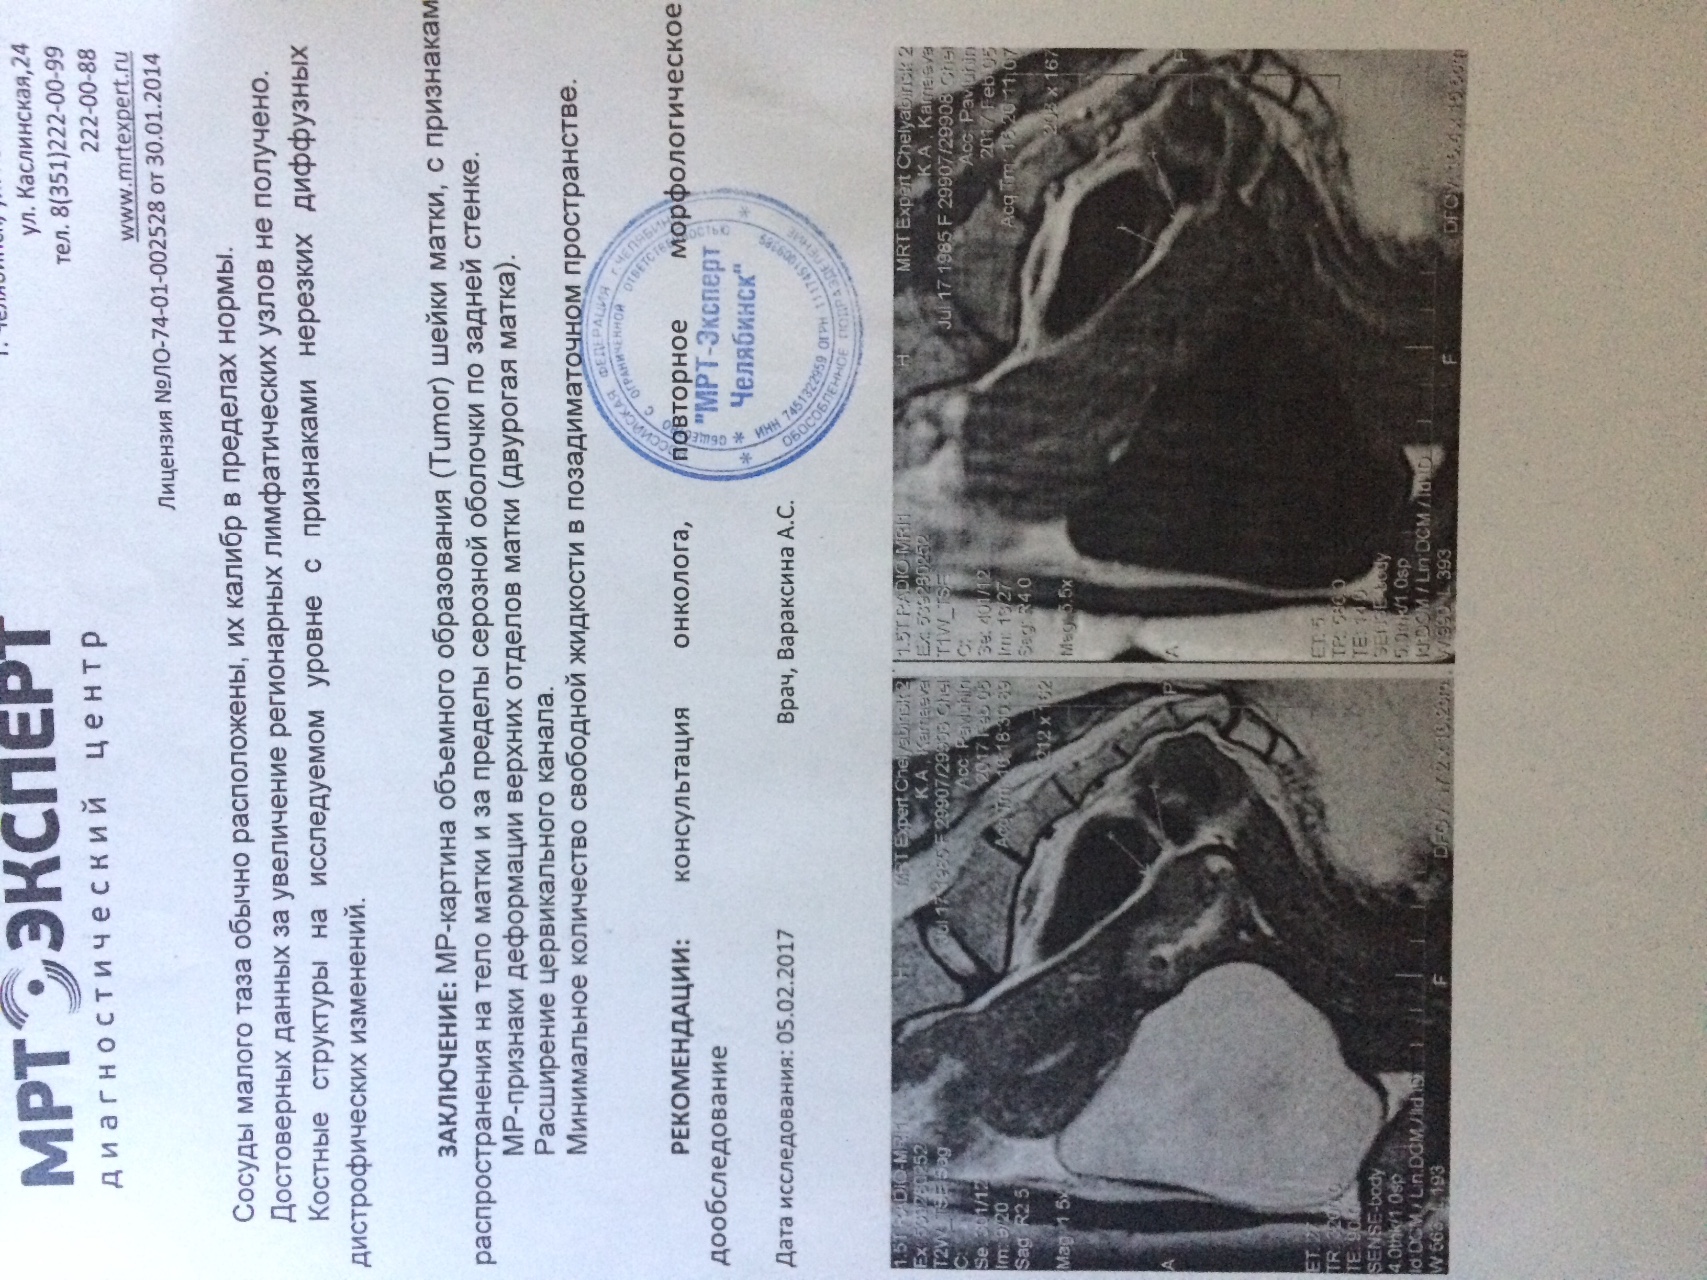

Злокачественная опухоль на матке заключение

Лейомиосаркома матки мрт

Примеры фото МРТ малого таза у женщин

Ниже представлены примеры фотографий МРТ малого таза у женщин, позволяющие увидеть, как выглядят снимки и какие изменения могут быть обнаружены специалистами.